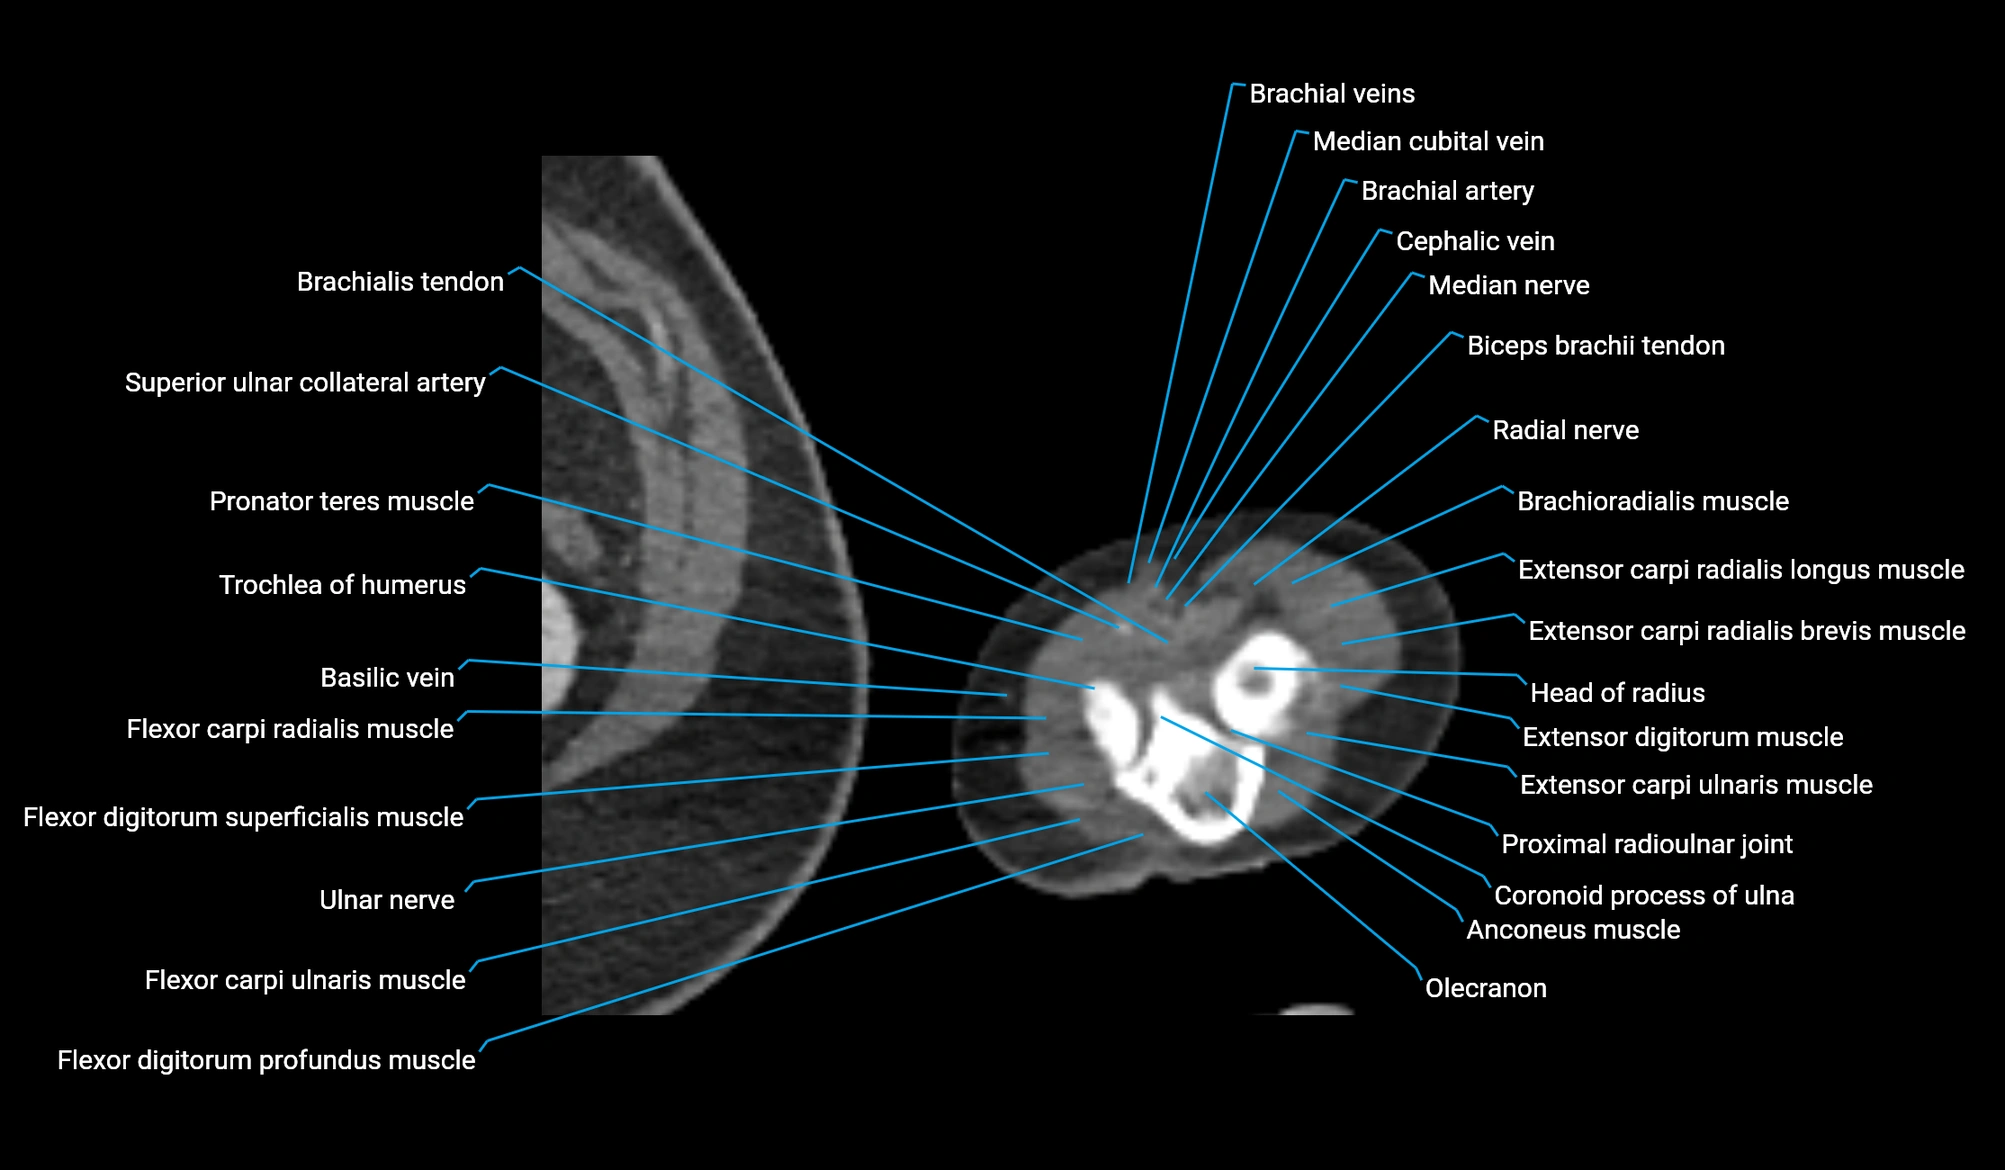

- Anconeus muscle

- Brachioradialis muscle

- Coronoid process of ulna

- Extensor carpi radialis brevis muscle

- Extensor carpi radialis longus muscle

- Extensor carpi ulnaris muscle

- Extensor digitorum muscle

- Flexor carpi radialis muscle

- Flexor carpi ulnaris muscle

- Flexor digitorum profundus muscle

- Flexor digitorum superficialis muscle

- Head of radius

- Median cubital vein

- Median nerve

- Olecranon

- Pronator teres muscle

- Proximal radioulnar joint

- Radial nerve

- Superior ulnar collateral artery

- Trochlea of humerus

- Ulnar nerve